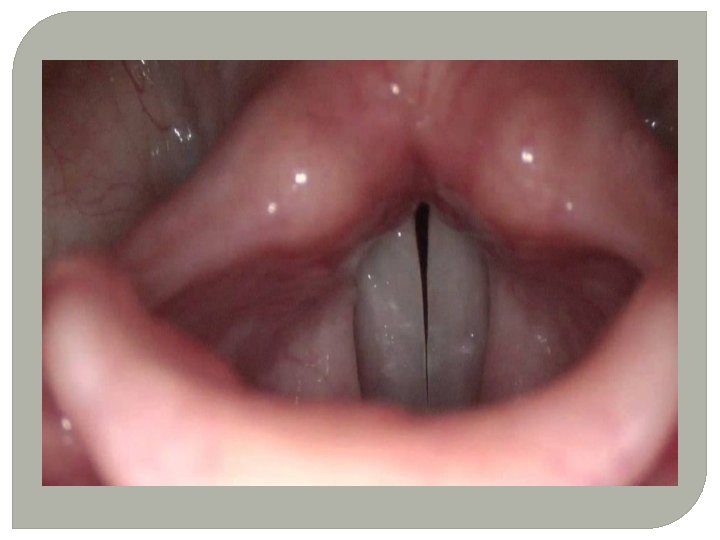

SESİN OLUŞUMU �SES TELLERİ: Ses telleri gırtlak yapısının içerisinde 3 tabakadan oluşan bir yapıdır. (kas yapısı, jölemsi yapı ve ses sinirleri) �Nefes alıp verme esnasında akciğerlerden gelen havanın, gırtlakta bulunan ses tellerinin arasından geçerken titreştirmesi sonucu oluşan titreşimlerdir.

NODÜL �Ses telleri iltihabı( sesin HATALI ve YOĞUN kullanımından kaynaklanan ses telleri üzerinde nasırımsı yapı) �En önemli ses hastalığıdır. !!!! �TEDAVİ: �İlaç tedavisi yanında bitkisel tedavi �Son çare Ameliyat.

�DİĞER SES HASTALIKLARI �Ses kistleri �Polipler �Ses felçleri

POLİP RAHATSIZLIĞI